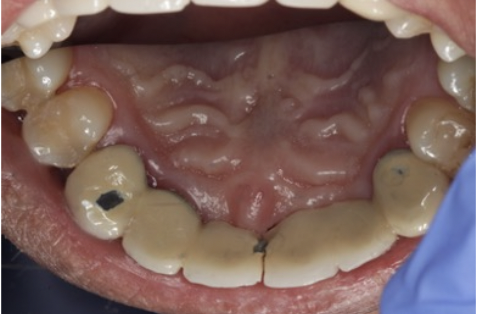

In this picture is a 6-unit bridge from #6-#11. Which of the following statements is false